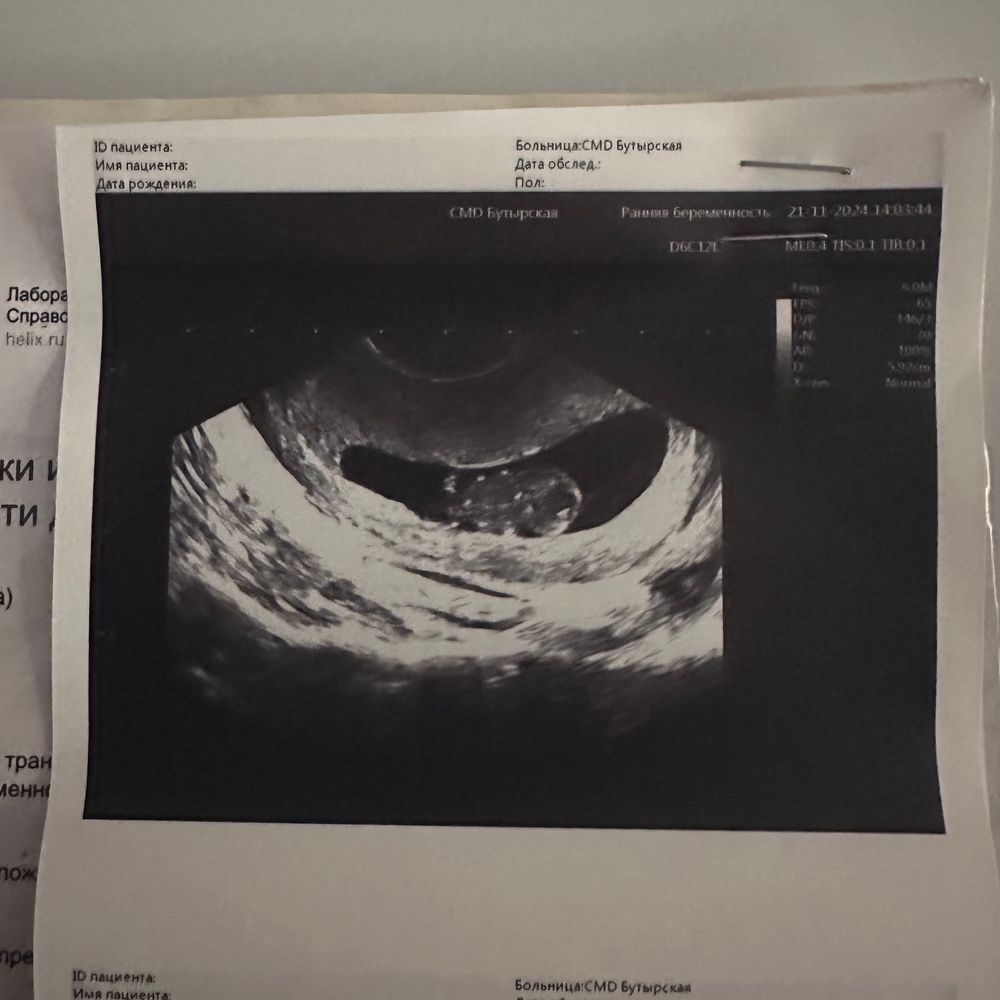

Бусинка растет. УЗИ 9н2д.

Изображение

Вчера была на узи, ибо очень переживала на счет зб на фоне того, что токс резко пропал, знаю, что это никак не влияет, ибо у некоторых и при зб вплоть до операции токс сох